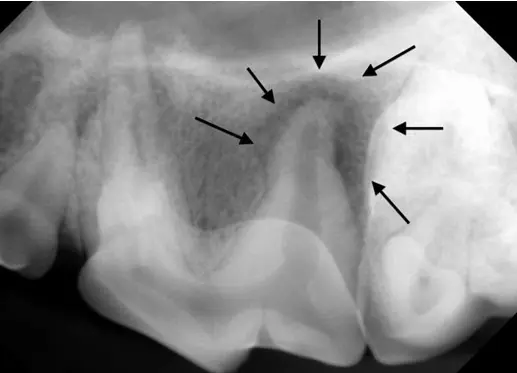

Below is the radiograph from last month, from an endodontically infected tooth. A classic periapical lucency can be seen around the distal root. For comparison, the second X-ray is from the contralateral tooth in the same patient, showing normal anatomy.

Dental radiograph of 208, showing a large lucent area surrounding the distal root.

For comparison, the dental X-ray taken of the same tooth on the other side shows the normal appearance of the bone and periodontal ligament space around the back root (arrows).